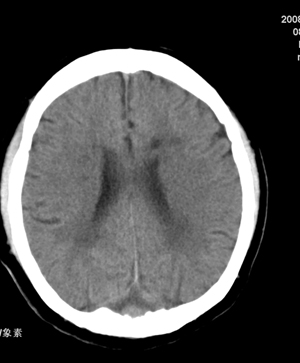

1.右基底节区脑软化灶。

2.右顶后部病变,脑膜瘤可能性大。

建议:强化扫描。

右侧基底节腔梗。

右顶后部血管畸形。

蛛网膜下腔出血。